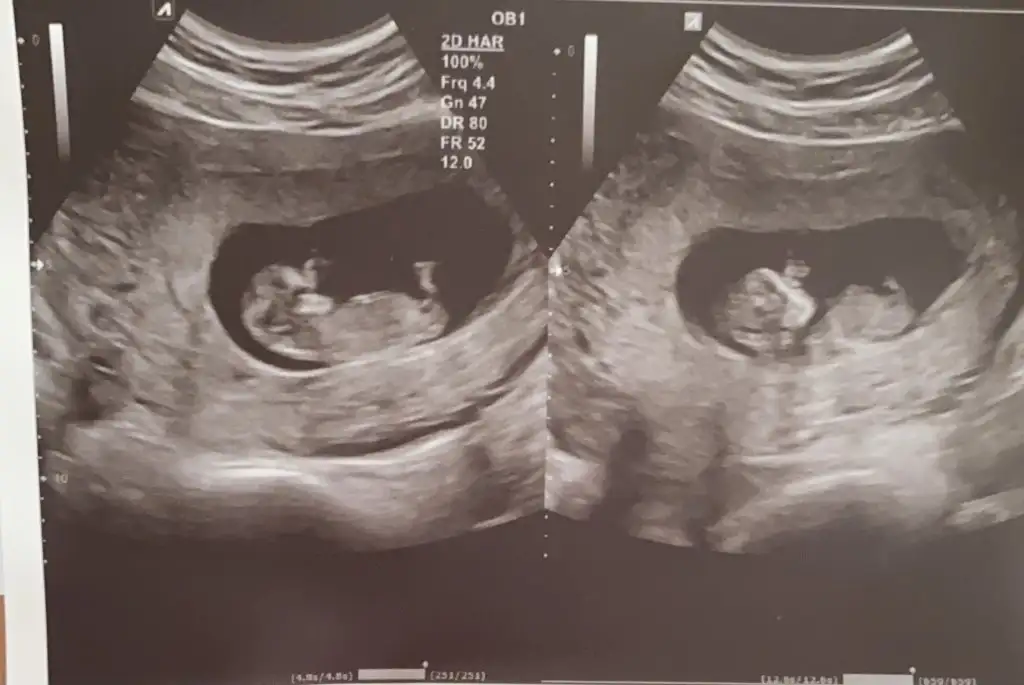

Canım ikiz bebeklerim ikisi de ayrı ☺Emin olmadım erkek gibi sanki başka USG paylaşın

Yanlış alıntılamışım canım pardonCanım ikiz bebeklerim ikisi de ayrı ☺